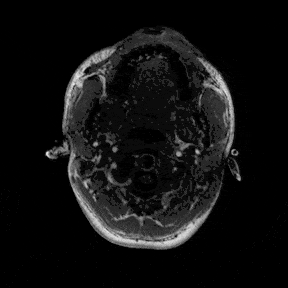

The most immediate way to inspect the MRI was just to scroll through it in the three standard anatomical planes.

This was the first surreal part of the project - watching slices of my own skull and recognising the big landmarks (the ventricles, the corpus callosum, the cerebellum, the hemispheres). However, at the same time, I was also aware that I was mostly pretending to know what I was looking at. I could tell that there was a lot more information buried in the scan, ready to be analysed.